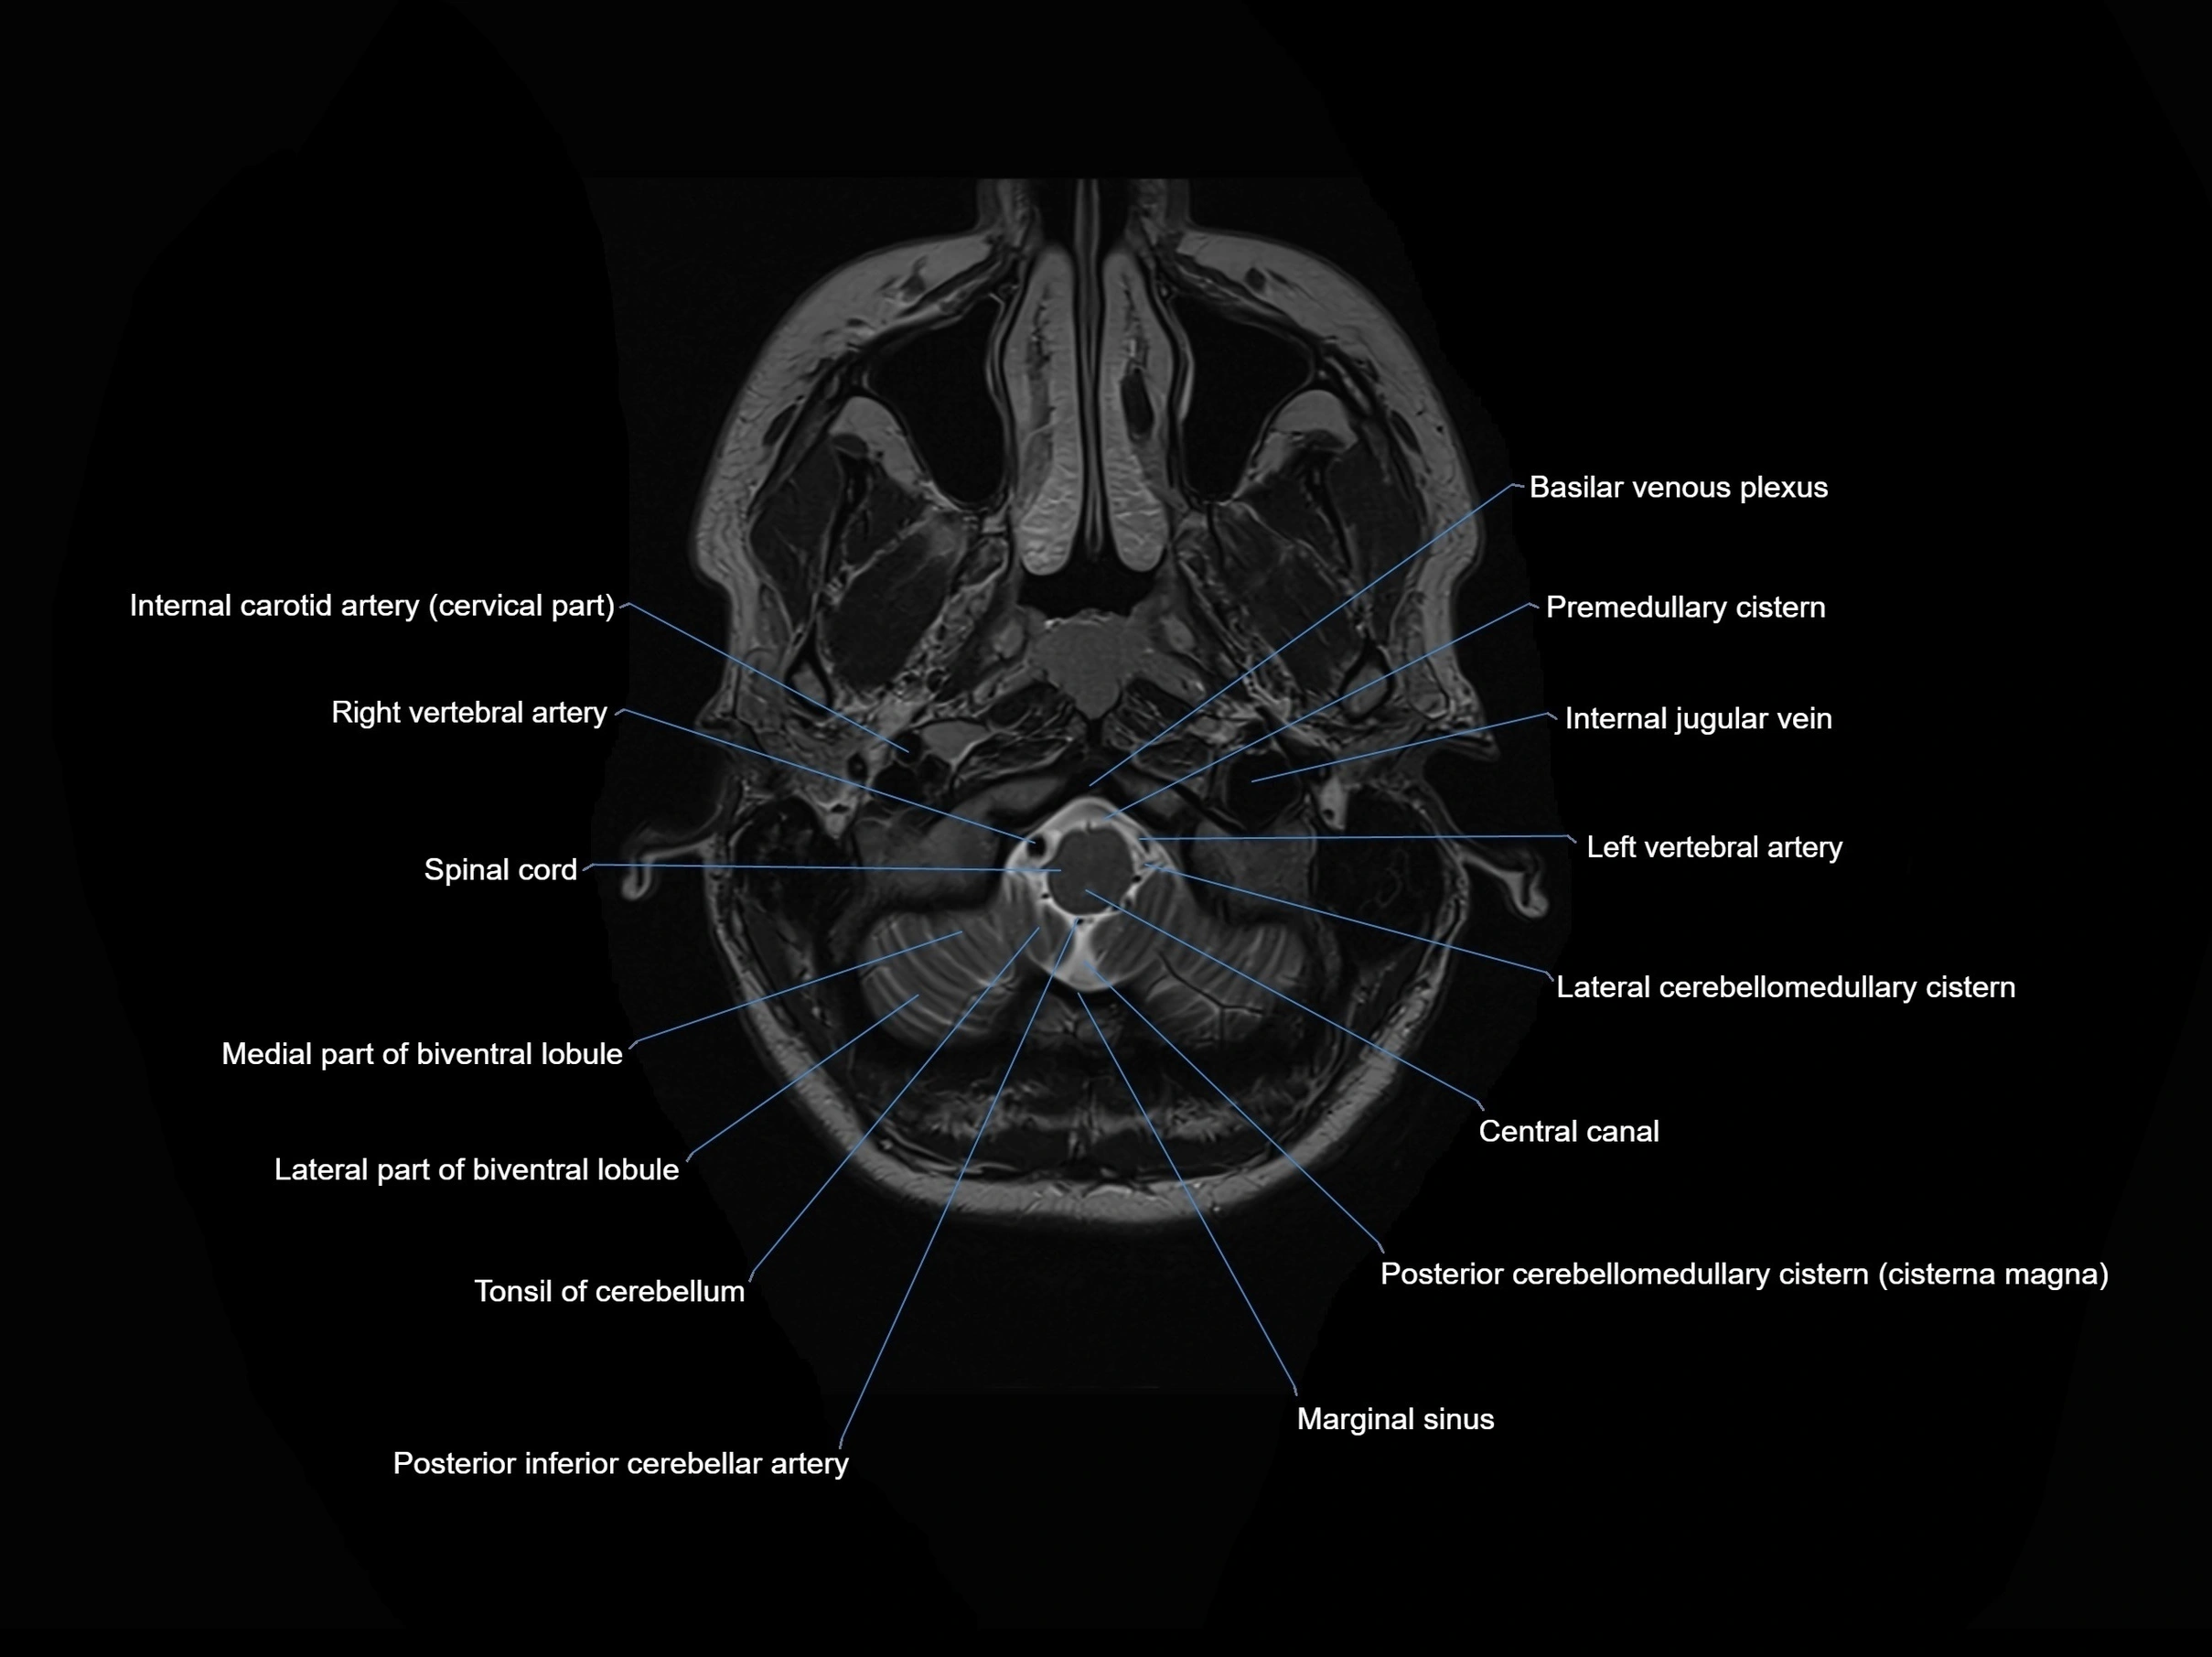

MRI images